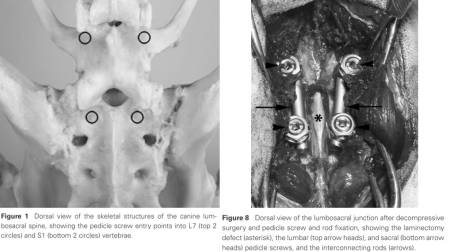

Pedikelschraube & Platte

winkelstabile Verplattung

- Smolders LA, Voorhout G, Ven R, Bergknut N, Grinwis GCM, Hazewinkel HAW, Meij BP (2012): Pedicle Screw-Rod Fixation of the Canine Lumbosacral Junction. Veterinary Surgery 41: 720-732.

- Toni C et al. (2021): Accuracy of Placement of Pedicle Screws in the Lumbosacral Region of Dogs Using 3D-Printed Patient-Specific Drill Guides

34(1):53-58.